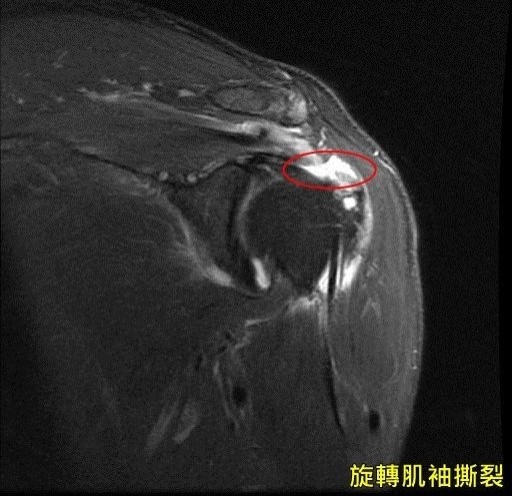

肩旋轉袖斷裂 肩袖撕裂 Rotator Cuff Tear

醫病 6旬婦肩痛以為50肩竟是旋轉肌袖撕裂作祟 即時新聞 自由健康網

旋轉肌袖撕裂多需手術修復 即時新聞 自由健康網